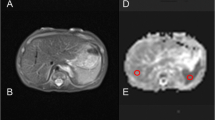

From the native DWI acquisition, ADC maps were obtained on the acquisition console (Syngo, Siemens Medical Solutions, Erlangen, Germany). Data was then transferred to Osirix (open source DiCOM viewer: http://www.osirix-viewer.com) for ADC measurements in different regions of interest (ROI). Circular ROIs were drawn manually and plotted on ADC maps for all cases by two independent readers blinded to one another’s findings and also to the post-mortem report. Where there was difficulty in identifying the delineation of the target organ, cross-referencing was made to the isovolumetric T2 sequences obtained during the same MRI examination for anatomical information. The readers read the cases once. Both readers were qualified paediatric radiologists with 7 years experience each.

The ROIs were placed on the following body locations (Fig. 2):

1)

Lung: obtained within the largest region of ‘normal’ lung parenchyma (i.e. non-consolidated regions for neonatal deaths, and for all cases—not including any pleural effusions).

2)

Myocardium: within the intraventricular septum or left ventricular muscle, whichever allowed the largest ROI volume to be obtained.

3)

Right renal cortex: avoiding any renal pelvis.

4)

Liver: within the right lobe of the liver to obtain the most representative ROI sample.

5)

Spleen: within the centre of the organ to include the largest ROI possible

6)

Right psoas muscle: used as a control value.

For each ROI, a mean ADC value (× 10−5 mm2/s) ± standard deviation (SD) was obtained. The circular area for the ROI was drawn to include as much of the target organ as possible, whilst maintaining a relative SD < 10% of the mean to ensure homogeneity, typically < 25mm2. Size-specific ROIs were used for each individual case rather than choosing a fixed ROI, due to the range of foetal sizes (weight and gestation range given in Table 1) in our sample size. Where a valid ADC value for an organ could not be obtained (either due to a small organ inclusion area on the ADC map or significant artefact), then this was left blank or unrecorded.